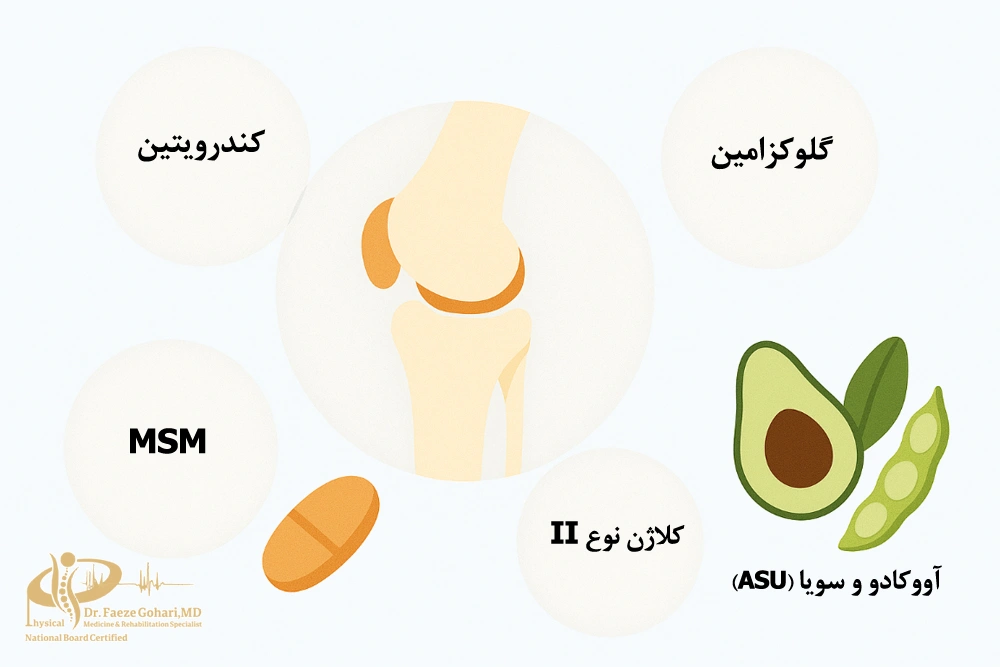

ترکیباتی مانند گلوکزامین، کندرویتین، کلاژن نوع II و MSM در این محصولات رایجاند و در مصرف بلندمدت میتوانند به بهبود حرکت مفصل و کاهش درد کمک کنند. البته میزان اثربخشی آنها به عواملی مانند شدت آسیب، سن، وزن و سبک زندگی بستگی دارد و در آسیبهای جدی نباید جایگزین مراجعه به متخصص طب فیزیکی یا درمان تخصصی شوند.

ترکیبات اصلی و ثابتشده در مکملهای غضروفساز

برخی ترکیبات در اغلب قرصها و مکملهای غضروفساز وجود دارند که پشتوانهی علمی قویتری دارند و بیشتر مورد استفاده قرار میگیرند. این مواد معمولاً در بهبود عملکرد مفصل، کاهش التهاب و پشتیبانی از بازسازی بافت غضروف نقش مؤثری ایفا میکنند. در ادامه، مهمترین آنها را معرفی میکنیم.

گلوکزامین (Glucosamine Sulfate / HCl)

کندرویتین (Chondroitin Sulfate)

MSM (متیلسولفونیلمتان)

کلاژن نوع II (Undenatured Collagen Type II)

ترکیب ضدالتهاب آووکادو و سویا (ASU)